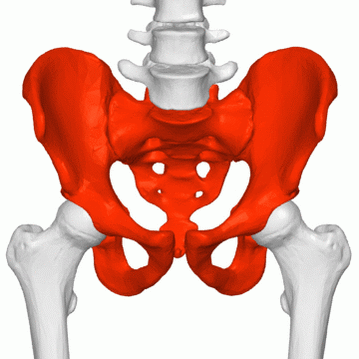

Кости таза

Основу таза образуют две тазовые кости, крестец и копчик, соединённые суставами пояса нижних конечностей в костное кольцо, внутри которого образуется полость, заключающая внутренние органы. До возраста 16—18 лет кости (подвздошная, лобковая и седалищная) соединены хрящами. Впоследствии происходит окостенение, и указанные кости срастаются между собой, образуя тазовую кость.

Парные тазовые кости спереди соединяются при помощи лобкового симфиза, а сзади прикрепляются ушковидными поверхностями к одноимённым образованиям крестца, образуя парные крестцово-подвздошные суставы. Каждая из тазовых костей в свою очередь образована тремя составляющими: подвздошной костью, седалищной костью и лобковой костью, тела которых на наружной поверхности образуют вертлужную впадину — суставную ямку для головки бедренной кости, с которой образуют тазобедренный сустав.

Парные тазовые кости вместе с анатомическими образованиями, идущими от них и таза к бедренной кости и бедру, посредством которых происходит прикрепление ног к позвоночнику (крестцу), образуют тазовый пояс (пояс нижних конечностей).